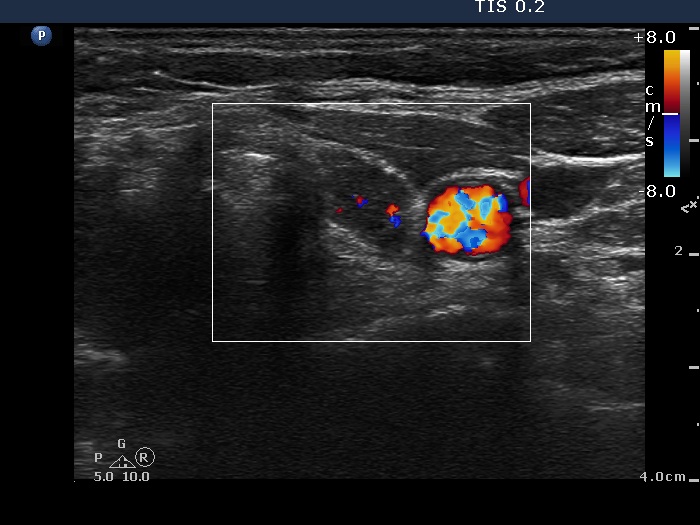

Left lobe, transverse scan, color Doppler mode. The vascularization is decreased.